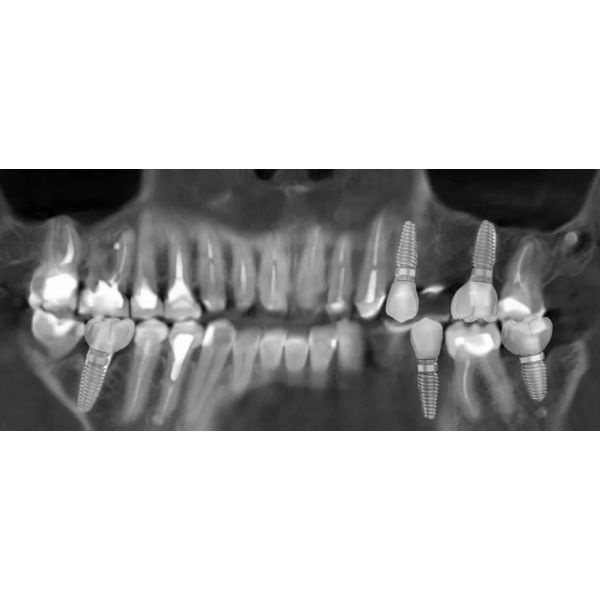

Когда суставные головки приняли нормальное положение, наступил этап изготовления постоянных конструкций. Из непротезированных зубов у пациентки остались только нижние 4 резца и 2 клыка.

За весь период реабилитации пациентке:

- вылечили периодонтит и кариес;

- сделали костную и десневую пластику;

- выровняли десневой контур;

- установили 5 имплантов;

- зафиксировали коронки и виниры на все зубы.